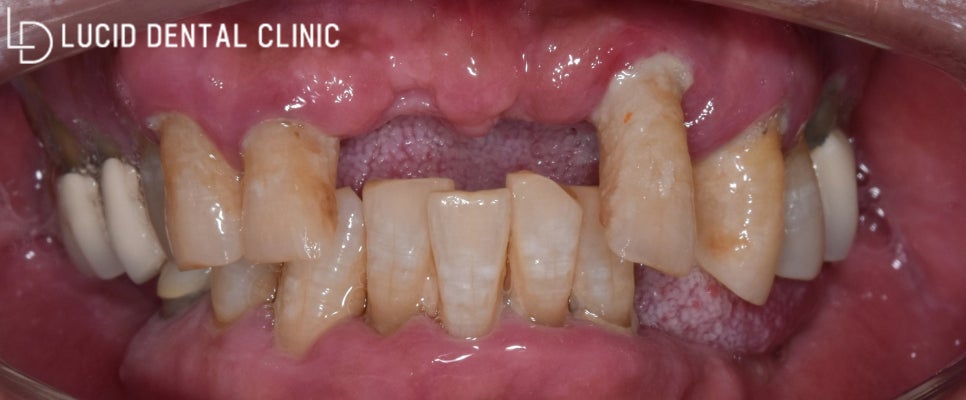

지금 보는 건 파노라마 방사선 사진인데요.

현재 하악(아래턱) 구치부(어금니)가 모두 발거됐고,

신경치료를 받은 곳은 치근단 병소가 나타났습니다.

그뿐만 아니라 상악(위턱)치아가 대부분 정출되어

제대로 된 곳에 위치하지 못하고 있었는데요.

이런 상태로는 올바른 교합이 이루어지지 않아

저작 기능에도 굉장히 불편했을 것으로 보입니다.

신논현역 루시드 치과 가 진단한 결과,

대부분 모두 발치해야 된다고 판단했는데요.